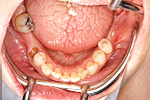

症例 3

下の顎

① 下の顎・治療前。歯が何もありません。

② 下の顎・インプラントの埋入後

③ 下の顎・セラミッククラウン、ブリッジセット状態

④ 治療後。前から見た状態

上の顎

① 上の顎・治療前。歯が4本しかありません。

② 上の顎・歯周治療の後。矯正治療で歯の位置を修正

③ 上の顎・インプラント埋入の状態

④ 上の顎・ハイブリッドセラミックブリッジセット状態

⑤ 治療後・前から見た状態

60才代 男性

総額:530万円(税別)

治療期間:2年

リスク副作用:経年的変化による補綴物の消耗。ブラッシング不足ですとインプラント周囲炎になります。